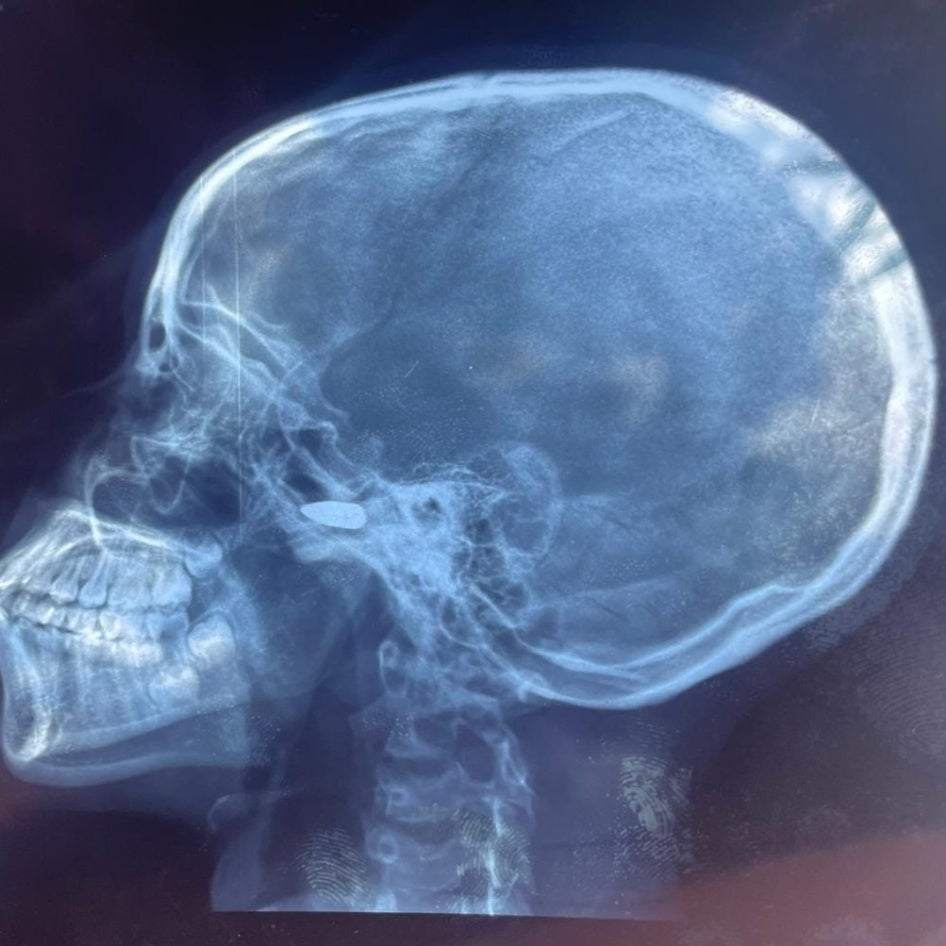

Radiographie d'une fille de 15 ans qui a été touchée à la tête par une balle perdue à Bébédja, au sud du Tchad, le 9 mai 2024, après l'annonce des résultats provisoires de l'election présidentielle au Tchad. © 2024 Private